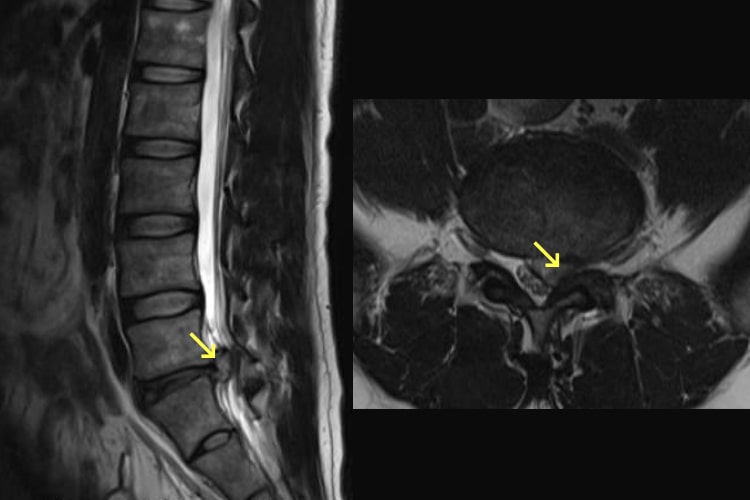

腰椎椎間板ヘルニア

20~50歳の青壮年期の男性に多く、腰や臀部が痛み、下肢に痺れや痛みが発生するほか、悪化すると下肢に力が入りにくくなります。徒手検査、レントゲン、MRIにより診断を行います。治療は、消炎鎮痛剤や神経痛を抑える薬の内服、外用薬、神経ブロック注射などを行います。痛みが強い時期にはコルセットを装着して安静を心がけ、痛みが軽くなれば牽引を行うといった理学療法も効果があります。こうした治療を行っても回復が見込めなければ手術療法となります。椎間板の摘出やヘルニアや髄核の切除などを行います。

腰部脊柱管狭窄症

60歳以上の男性や腰椎すべり症のある方でよくみられます。もっとも特徴的な症状は、歩行と休息を繰り返す間歇性跛行(かんけつせいはこう)です。原因としては、加齢、労働、あるいは脊椎の病気による影響で変形した椎間板と、脊椎や椎間関節から突出した骨棘などにより脊柱管が狭くなり、そこで神経が圧迫されるためと考えられています。腰部脊柱管狭窄症では腰痛はあまり強くなく、安静にしている時にはほとんど症状はありません。少ない距離なら歩けるのですが、立ったり・歩いたりしているとお尻や太ももの部分が痛くなって歩けなくなります。けれども少ししゃがんで休めば、楽になって再び歩けるようになります。進行すると、下肢の力が落ちたり、膀胱直腸障害が出現します。腰部脊柱管狭窄症の治療では、保存療法と手術療法があります。初期は消炎鎮痛剤や神経の血行を良くする薬の内服、外用薬、神経ブロック注射などの保存療法を行います。こうした保存療法の効果が見られない場合は手術療法が適応になります。